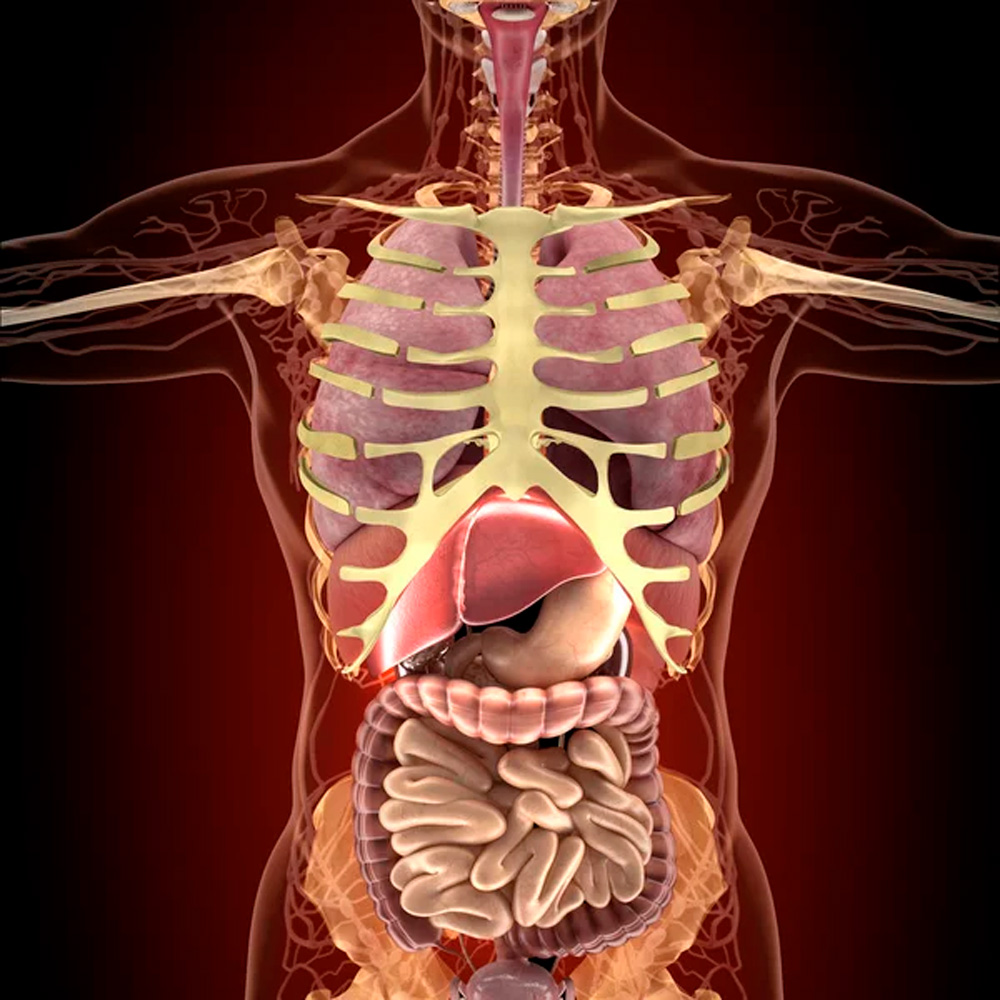

Para uma ereção mais fácil e duradoura, o Fênix Grego age inibindo a enzima PDE5, que é responsável por degradar uma substância chamada guanosina monofosfato cíclico (GMPc). O GMPc é responsável pelo relaxamento dos músculos lisos no tecido erétil do pênis, permitindo o aumento do fluxo sanguíneo. Esse é o segredo e é como iremos te ajudar!